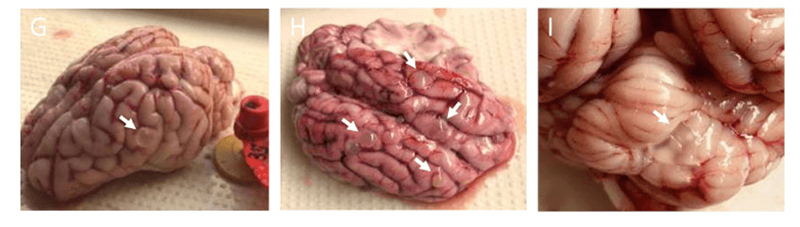

Porcine model of neurocysticercosis by intracarotid injection of Taenia solium oncospheres: Dose assessment, infection outcomes and serological responses. Gianfranco Arroyo et al., PLOS Neglected Tropical Diseases, 2022. [These pictures are three of nine images on Figure 1.] | Creative Commons—Attribution 4.0 International—CC BY4.0

Brains of pigs in an NIH-funded foreign lab show signs of infection by pork tapeworm, a parasite injected by the experimenters into the animals’ carotids.